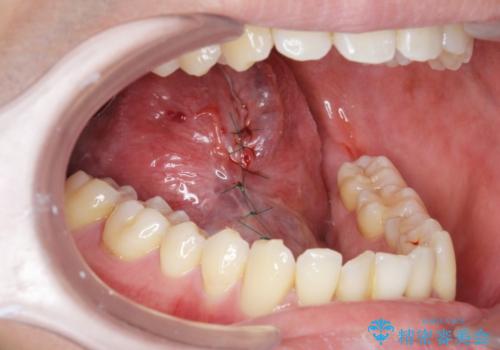

- 舌の動きが舌小帯により制限され、滑舌の改善を求めて来院されました。

形成手術を行うことで、舌の動きをより自由に行うことが期待できます。

発音しづらかった、サ行・タ行・ナ行の音が改善され喜んでいただくことができました。